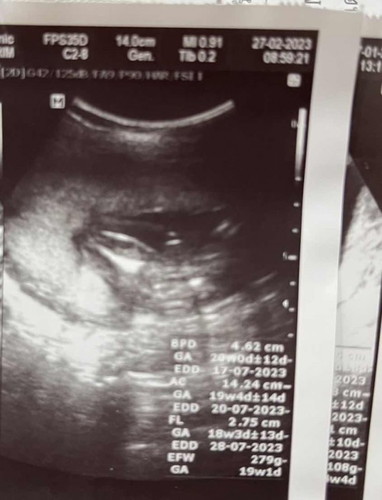

แบบนี้เพศชายแน่ใช่ไหมค่ะ

รูปสองไข่กลม จู๋ยื่นชัดเจนค่ะ

ผู้ชายชัดเจนค่า

กำลังตั้งครรภ์